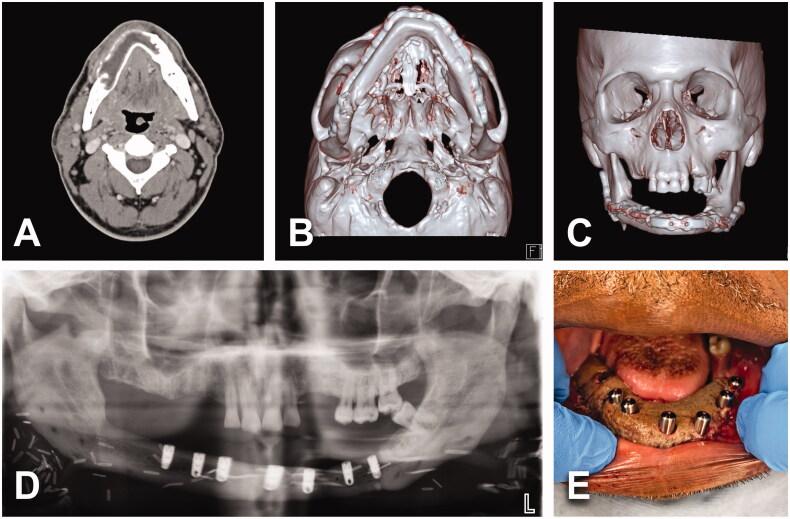

We studied 21 patients who underwent radical ameloblastoma excision followed by immediate reconstruction. Comorbidities, consumption of alcohol and/or tobacco and BMI status did not contribute to an unfavorable outcome. Giant ameloblastoma (≥5 cm) and/or tumor involving bony curvatures increased surgical complexity, the incidence of complications and hospital stay.

我们研究了21例接受成釉细胞瘤根治性切除并立即进行重建的患者。合并症、酒精和/或烟草消费以及体重指数状况并未导致不良预后。巨大成釉细胞瘤(≥5厘米)和/或累及骨弯曲的肿瘤增加了手术复杂性、并发症发生率和住院时间。